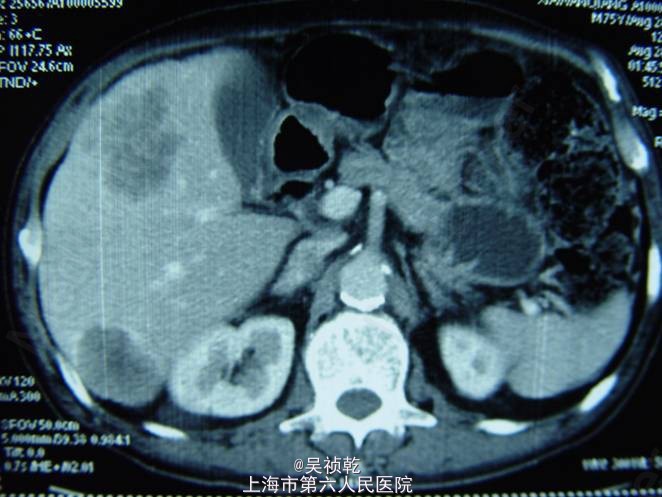

查体:浅表淋巴结(-)既往无重大疾病,体重下降5kg,肿瘤CEA>1500 ug/L。胸部CT :左下肺占位,考虑转移。上腹部CT :肝脏多发转移。盆腔CT :直肠肿物,伴不全肠梗阻。

术前诊断:直肠癌伴肝肺转移(肝脏多发,肺单发) 行直肠癌TME手术:术中探查:肝脏多发转移结节,最大者4cm, 无腹水及腹盆腔种植结节; 直肠肿瘤距肛门8cm,侵犯浆膜外脂肪组织。 病理:溃疡型管状腺癌II级,4.5*3.5*2cm,侵至肠壁全层,达肠周脂肪组织,肠周淋巴结转移: 6/12,肠系膜动脉根部0/2淋巴管(+)神经周围(+)血管(+)。K-ras检测:野生型 术后行化疗方案为:FOLFOX 4+Cetuximab (q2wk * 6次) 后评估肿瘤部分缓解,6次化疗结束后改为XELOX / q3wk*6次,评估肿瘤无进展。 下图可见复查的影响学资料相比化疗前肿瘤有明显缩小。